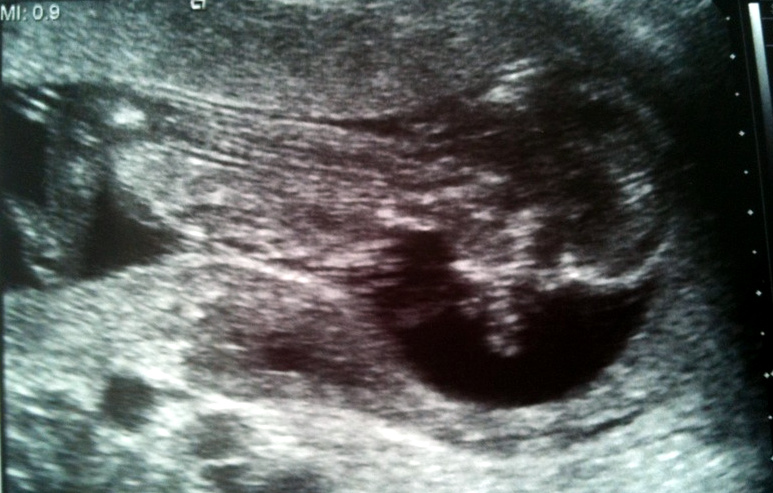

Úplně první oznámení (15. týden)

Mám se tu báječně. Místa tu mám ještě dost, i kdyz už mám 9 centimetrů. To je asi tolik!

Váhu se svými 50 gramy asi ještě nestrhnu… ale dělám, co můžu!

Papa, já, Verča a Ivan